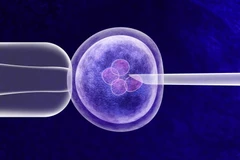

Trong 3 ngày, quả thận mới được nối vào mạch máu của bệnh nhân và được đặt bên ngoài cơ thể của người này để các nhà nghiên cứu có điều kiện giám sát, kiểm tra.

Nhóm nghiên cứu của tiến sỹ Montgomery đưa ra giả thuyết rằng việc tách bỏ một loại carbonhydrate, gây ra sự đào thải, trong gene lợn sẽ giải quyết được vấn đề đào thải của cơ thể người.

Con lợn được biến đổi gene, có tên là GalSafe, được công ty Revivicor thuộc tập đoàn United Therapeutics của Mỹ, tạo ra. Nó đã được Cục quản lý thực phẩm và dược phẩm Mỹ (FDA) phê duyệt vào tháng 12/2020 để sử dụng làm thực phẩm cho người bị dị ứng thịt và là một nguồn tiềm năng của liệu pháp điều trị cho con người.